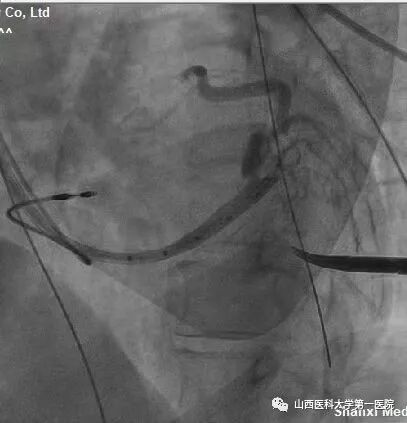

该患者为老年女性,主因反复间断胸闷10余年,加重1周入院。完善相关检查后提示:窦性心律,QRS波宽度187ms、完全左束支传导阻滞形态;心脏彩超显示:左室射血分数:25%,  左室舒末内径:72mm,符合ESC2021CRT指南I类适应证。术中,冠状窦静脉造影发现左室电极靶静脉(左室侧静脉)迂曲,双导丝导丝(Runthrough NS和Pilot50)均无法通过,采用逆向导丝技术,从后静脉逆向进入迂曲的静脉分支及侧支,成功进入左室侧静脉。